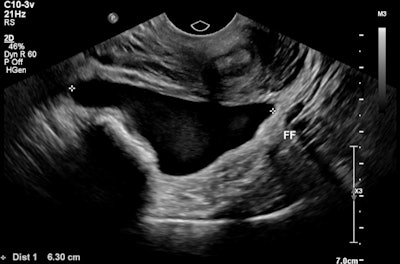

A 32-year-old female presented with severe constant left lower abdominal pain, per vaginal spotting and nausea. A pelvic ultrasound performed at six weeks' gestation demonstrated a viable intrauterine gestation and a small perigestational hematoma. A heterogeneous mass was noted abutting the left ovary. It featured peripheral vascularity, but no internal vascularity. There was small-volume pelvic free fluid with low-level internal echoes consistent with hemoperitoneum (see three images below).

Intrauterine gestational sac with fetal pole. All images courtesy of Dr. Jeffrey Alexis and Dr. Patricia Deonarine, presented at RANZCR ASM 2022.